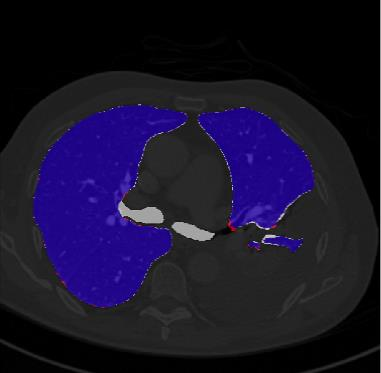

Segmentation of lung tissue in computed tomography (CT) images is a precursor to most pulmonary image analysis applications. Semantic segmentation methods using deep learning have exhibited top-tier performance in recent years. This paper presents a fully automatic method for identifying the lungs in three-dimensional (3D) pulmonary CT images, which we call it Lung-Net. We conjectured that a significant deeper network with inceptionV3 units can achieve a better feature representation of lung CT images without increasing the model complexity in terms of the number of trainable parameters. The method has three main advantages. First, a U-Net architecture with InceptionV3 blocks is developed to resolve the problem of performance degradation and parameter overload. Then, using information from consecutive slices, a new data structure is created to increase generalization potential, allowing more discriminating features to be extracted by making data representation as efficient as possible. Finally, the robustness of the proposed segmentation framework was quantitatively assessed using one public database to train and test the model (LUNA16) and two public databases (ISBI VESSEL12 challenge and CRPF dataset) only for testing the model; each database consists of 700, 23, and 40 CT images, respectively, that were acquired with a different scanner and protocol. Based on the experimental results, the proposed method achieved competitive results over the existing techniques with Dice coefficient of 99.7, 99.1, and 98.8 for LUNA16, VESSEL12, and CRPF datasets, respectively. For segmenting lung tissue in CT images, the proposed model is efficient in terms of time and parameters and outperforms other state-of-the-art methods. Additionally, this model is publicly accessible via a graphical user interface.